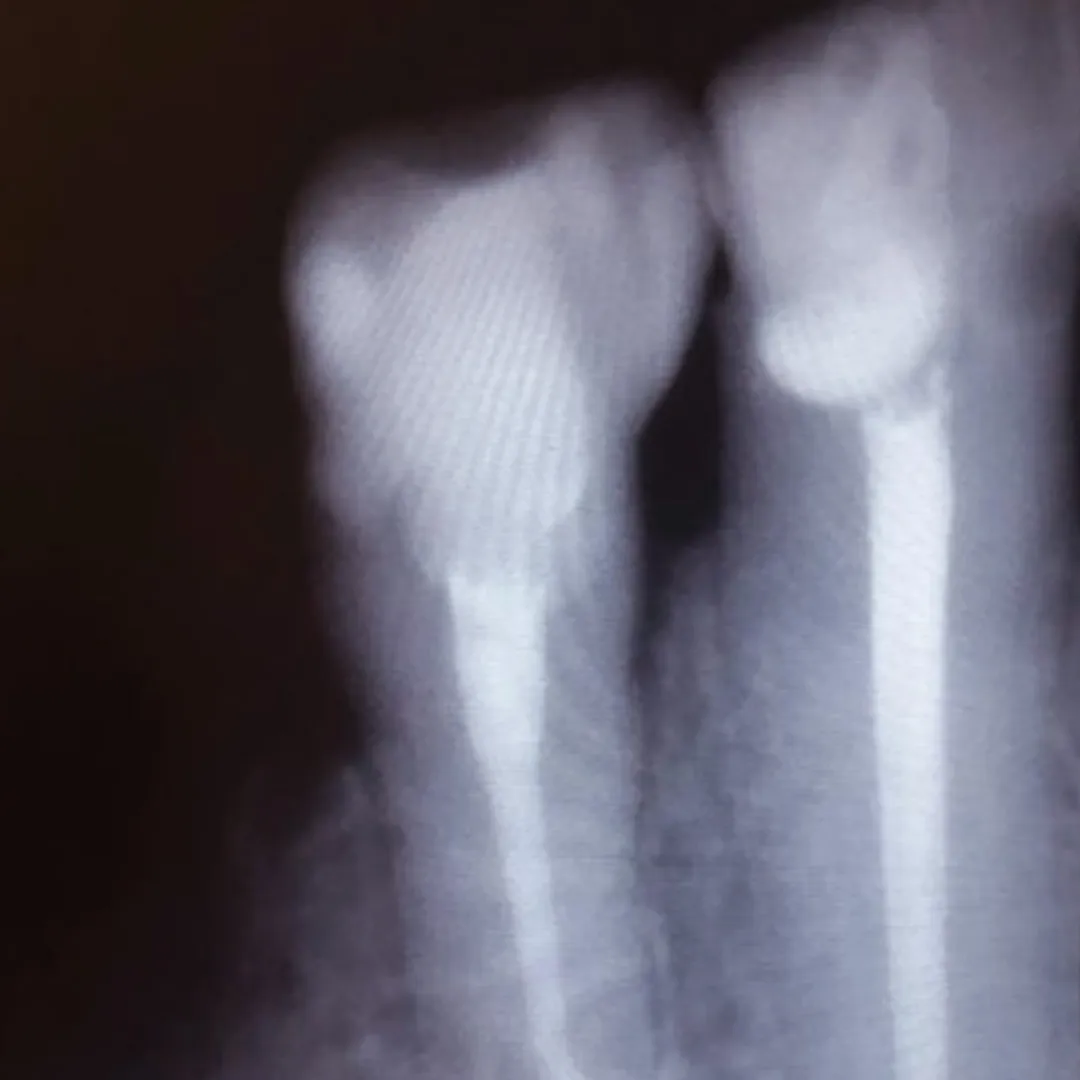

В «Стоматологию комфорта» обратилась пациентка с жалобами на эстетические дефекты 3.2, 3.1, 4.1 зубов. В процессе осмотра врач Серебрякова Мария Борисовна диагностировала хронический средний кариес зубов. Врач сделала заключение о целесообразности лечения и реставрации зуба при помощи композита Estelite.